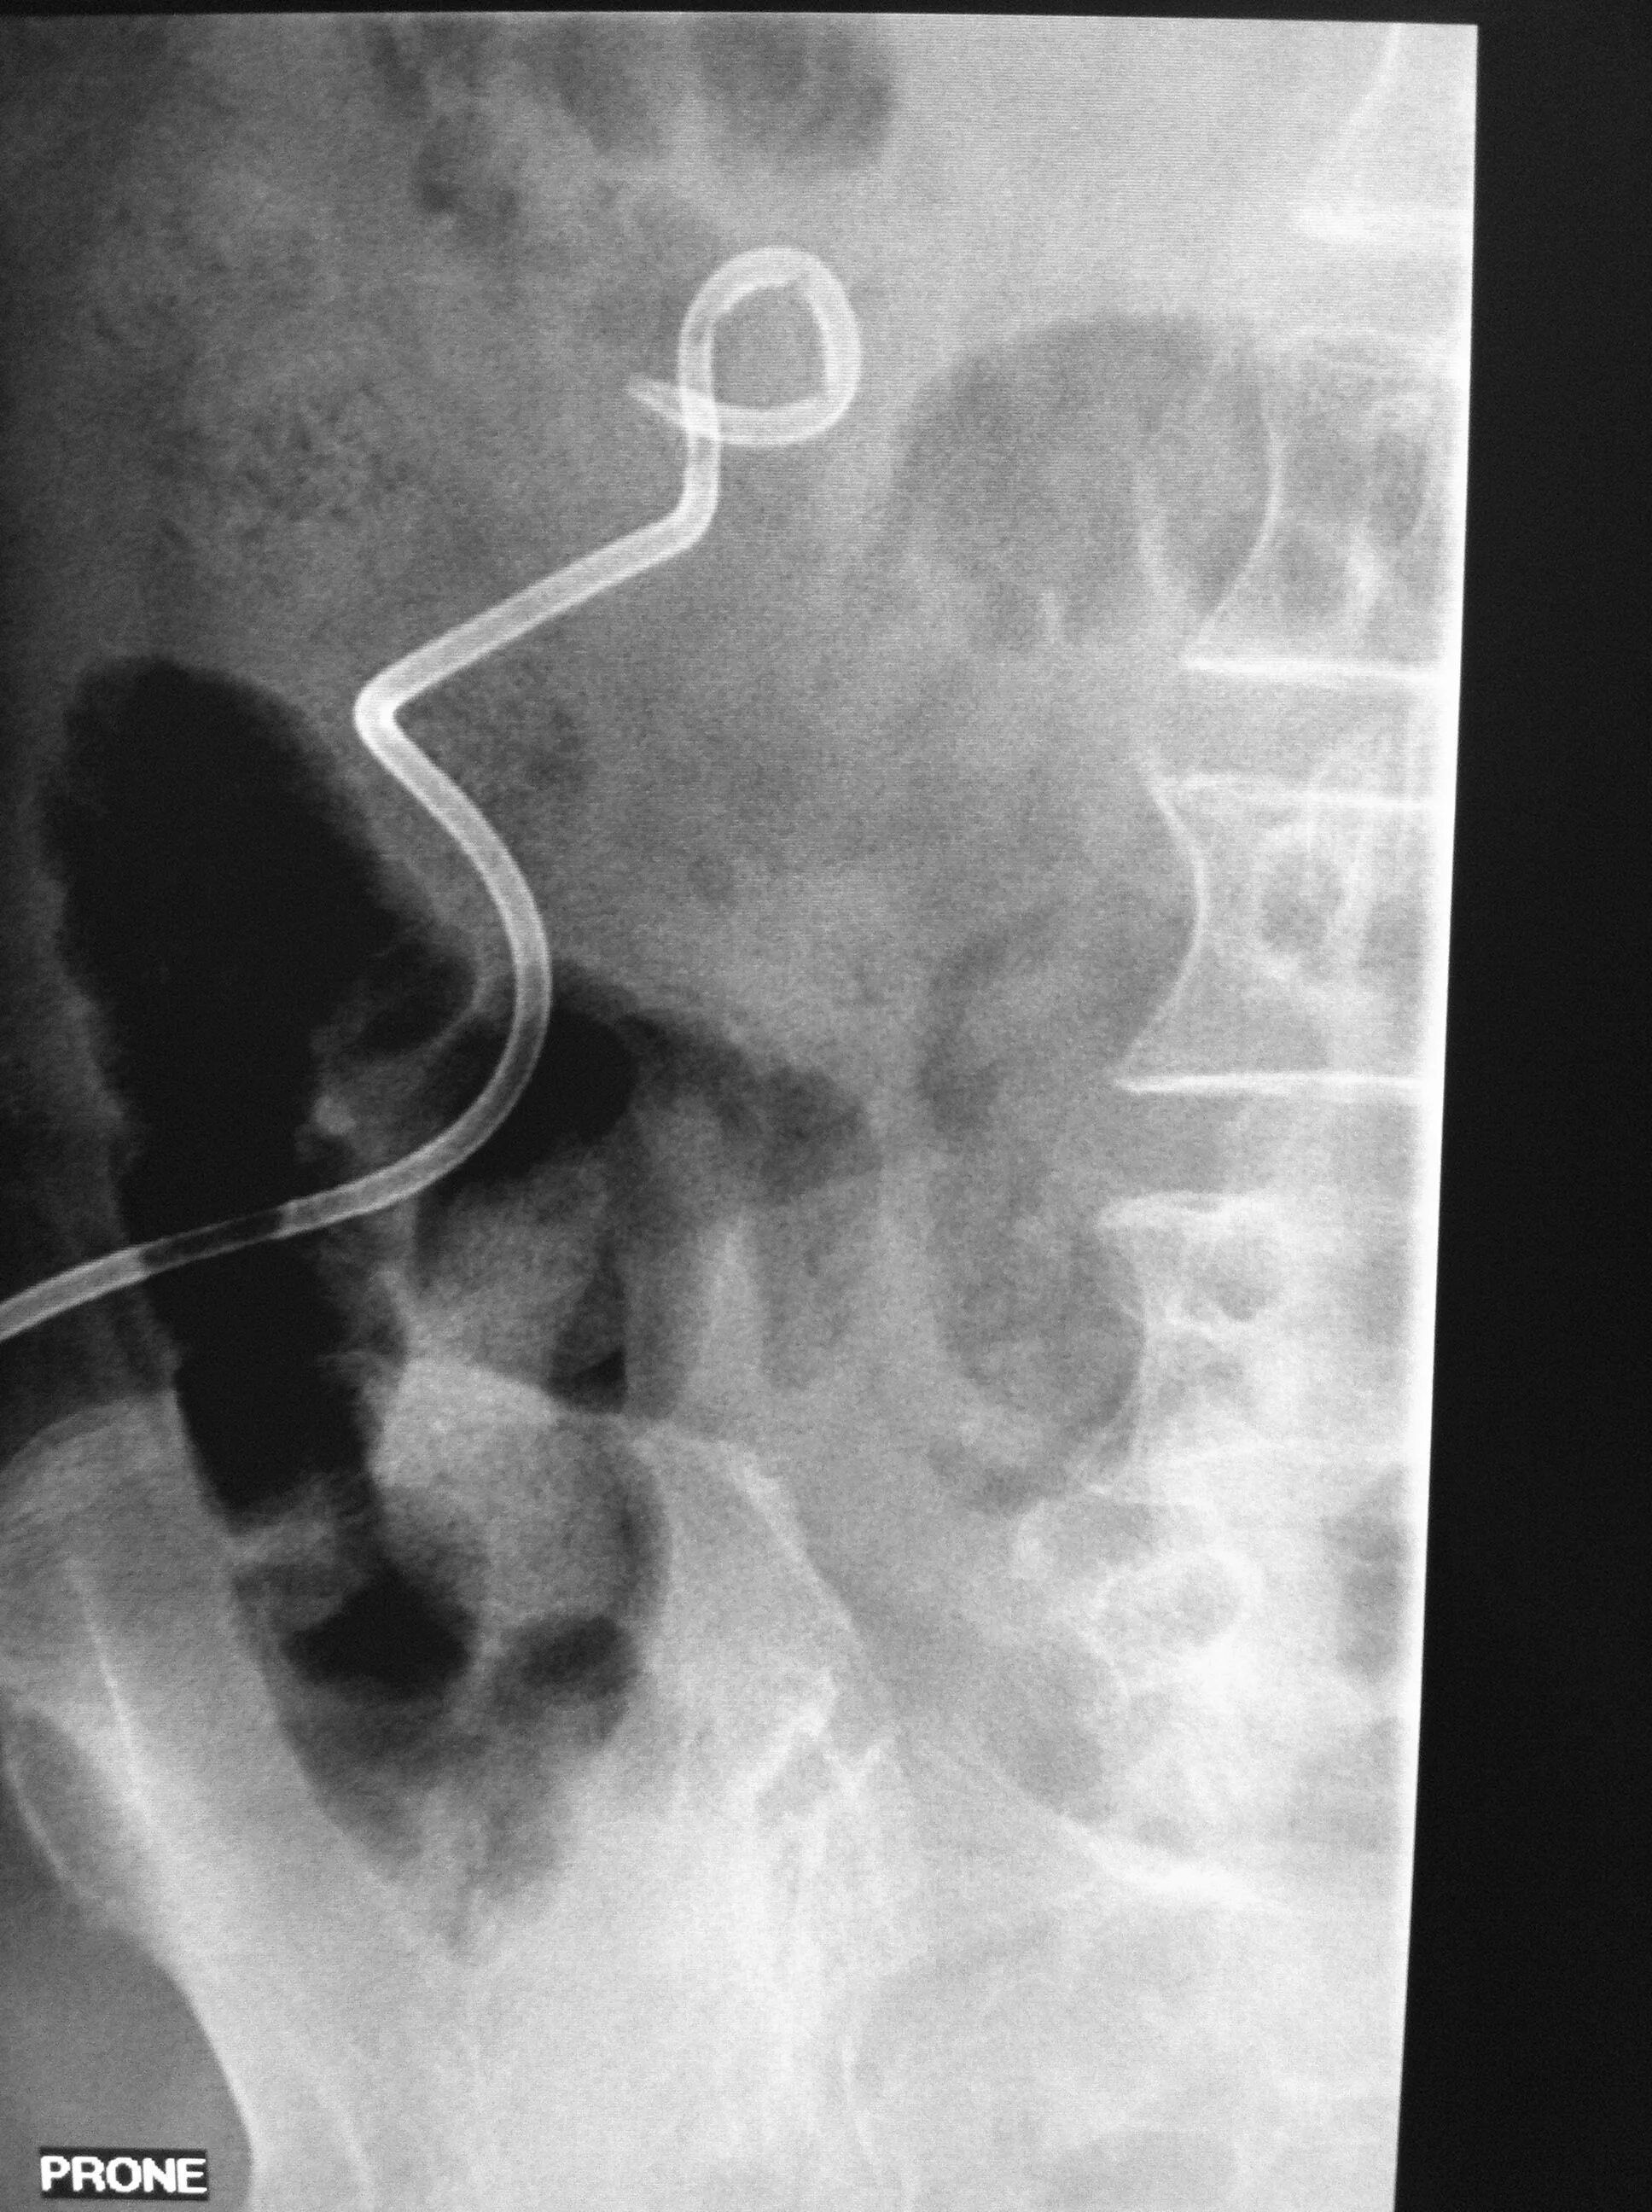

Нефростома в почке что это